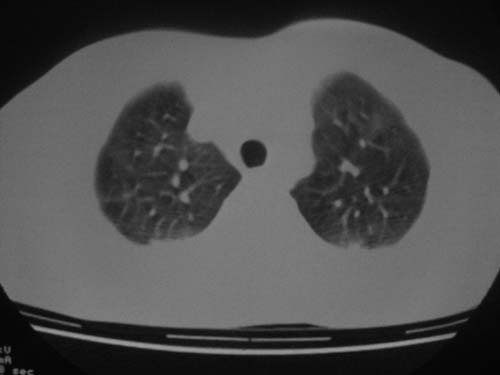

这是第五天拍的ct,纵隔窗我没都传,实在是太费时,请教各位老师,此病人有肺水肿吗?帮忙分析一下

1)双侧创伤性湿肺。2)双侧胸腔积液。

跟主治医生讨论病例

结果:病人刚入院水电解质紊乱,治疗期间大量输液,而且速度较快,正如4.5楼那样说的引起肺水肿,对症治疗后病情好转,